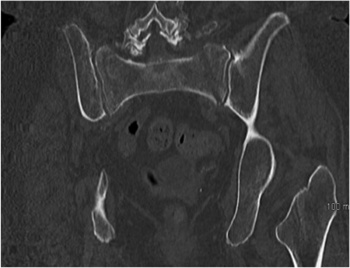

The sacroiliac joints are composed of the sacrum wedged between the ilia. It is the largest axial joint in the human body, with a surface area of approximately 17.5cm2. The morphology of the SIJ not only changes with age but it also varies greatly in size, shape and contour from side to side as well as between individuals.

The surface of the joint is flat until after puberty. By age 30, bony ridges are present on the articular surface of the ilium. With time the synovial articular surfaces erode and the synovial cleft narrows. The joint is supported by numerous ligaments, muscle and fascia.

Insufficiency sacral fractures in the older osteoporotic patient may occur with little or no trauma, and can be difficult to visualise on plain radiographs. Stress fractures have been reported in athletes due to repetitive microtrauma caused by impact loading over long periods of frequent physical exertion.